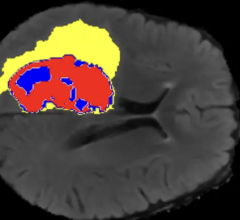

April 30, 2025 – Viz.ai, the leader in AI-powered disease detection and intelligent care coordination, has launched Viz ...